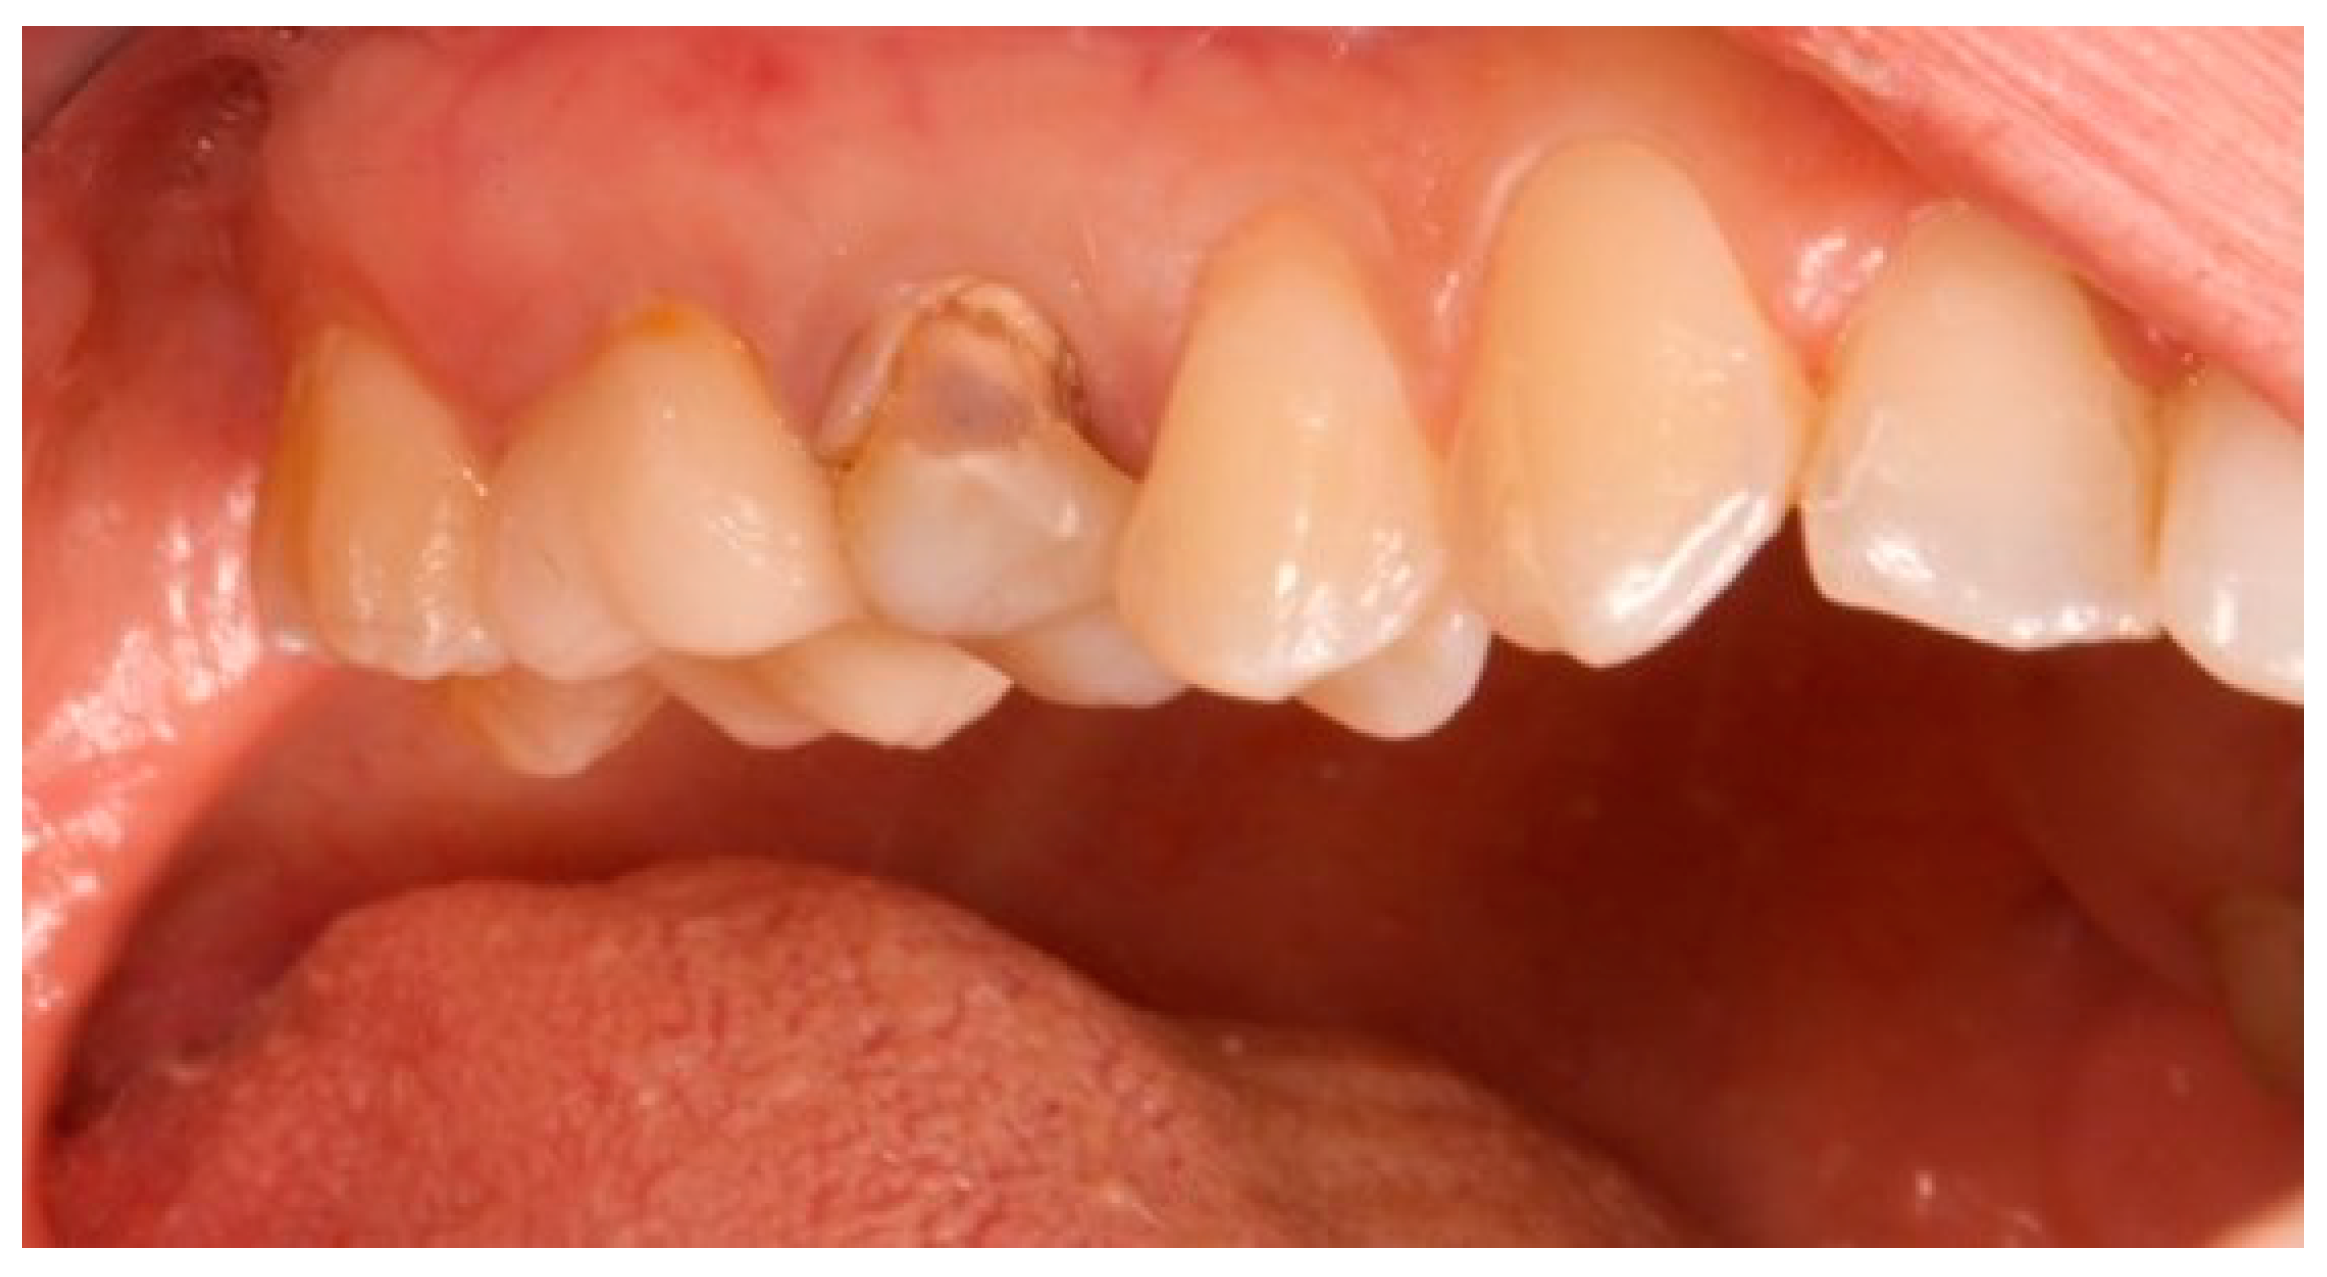

The primary outcome measure was the maintenance of peri-implant soft tissue architecture over a period of five years, assessed by measuring the distance between the peri-implant soft tissue margin (defined as the gingival and peri-implant connective tissue) and the implant fixture surface (defined as the surface of the implant that is surgically placed into the jawbone) at baseline (T0), three months (T1), one year (T2), and five years (T3). T0 represents the situation after the implant insertion. Upper premolars (teeth 1.4 and 1.5) and molars (teeth 1.6 and 1.7) designated for extraction had ≥5 mm apical bone, ≥12 mm height, ≥5.5 mm alveolar bone thickness, and D2 or D3 bone quality (Misch classification). Teeth lacking vestibular/palatal cortical bone, with periapical/periodontal lesions, or Class B/C (Tarnow classification) were excluded (Figure 1, Figure 2 and Figure 3A).

Figure 1.

Vestibular view prior to implant insertion of tooth 1.5.